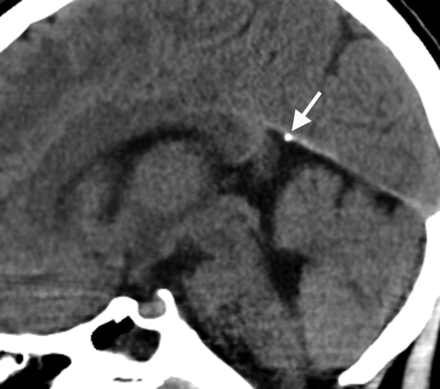

Dural calcifications were rare, present in only 1% (n = 6; age range, 2.9–8.7 years; median, 6 years; Fig 4). The tentorium was the most common dural site to calcify (n = 4) followed by the falx cerebri (n = 2).

Midline sagittal head CT image from an 8-year-old child obtained for headache, demonstrating dural calcifications along the anterior margin of the cerebellar tentorium (arrow).

Although extremely rare, the CT prevalence of childhood dural calcifications remains a subject without strong support in the literature. In a series of 970 trauma patients, Ratcliffe et al23 found dural calcifications in >20% of men older than 30 years and women older than 50 years on skull radiography; attenuated calcifications were present in less than 2% of those younger than 40 years. Kendall and Cavanagh20 found dural calcifications in 0.8% of patients 0–15 years of age. Dural calcifications were rare in our study, occurring in 1%. Posttraumatic dural calcifications rarely occur but are not unexpected after a calvarial breach from penetrating trauma and surgical intervention. Indeed, most of our patients with dural calcifications had previous craniotomies (4/6). The other 2 presented with headache (9 years of age) and head trauma (4 years of age). The tentorium was the most common area to calcify. Extensive dural calcifications in young patients should raise suspicion for pathologic conditions, including basal cell nevus syndrome, meningiomas, sequelae of prior subdural or epidural hemorrhage, and calcium/phosphate imbalance.24